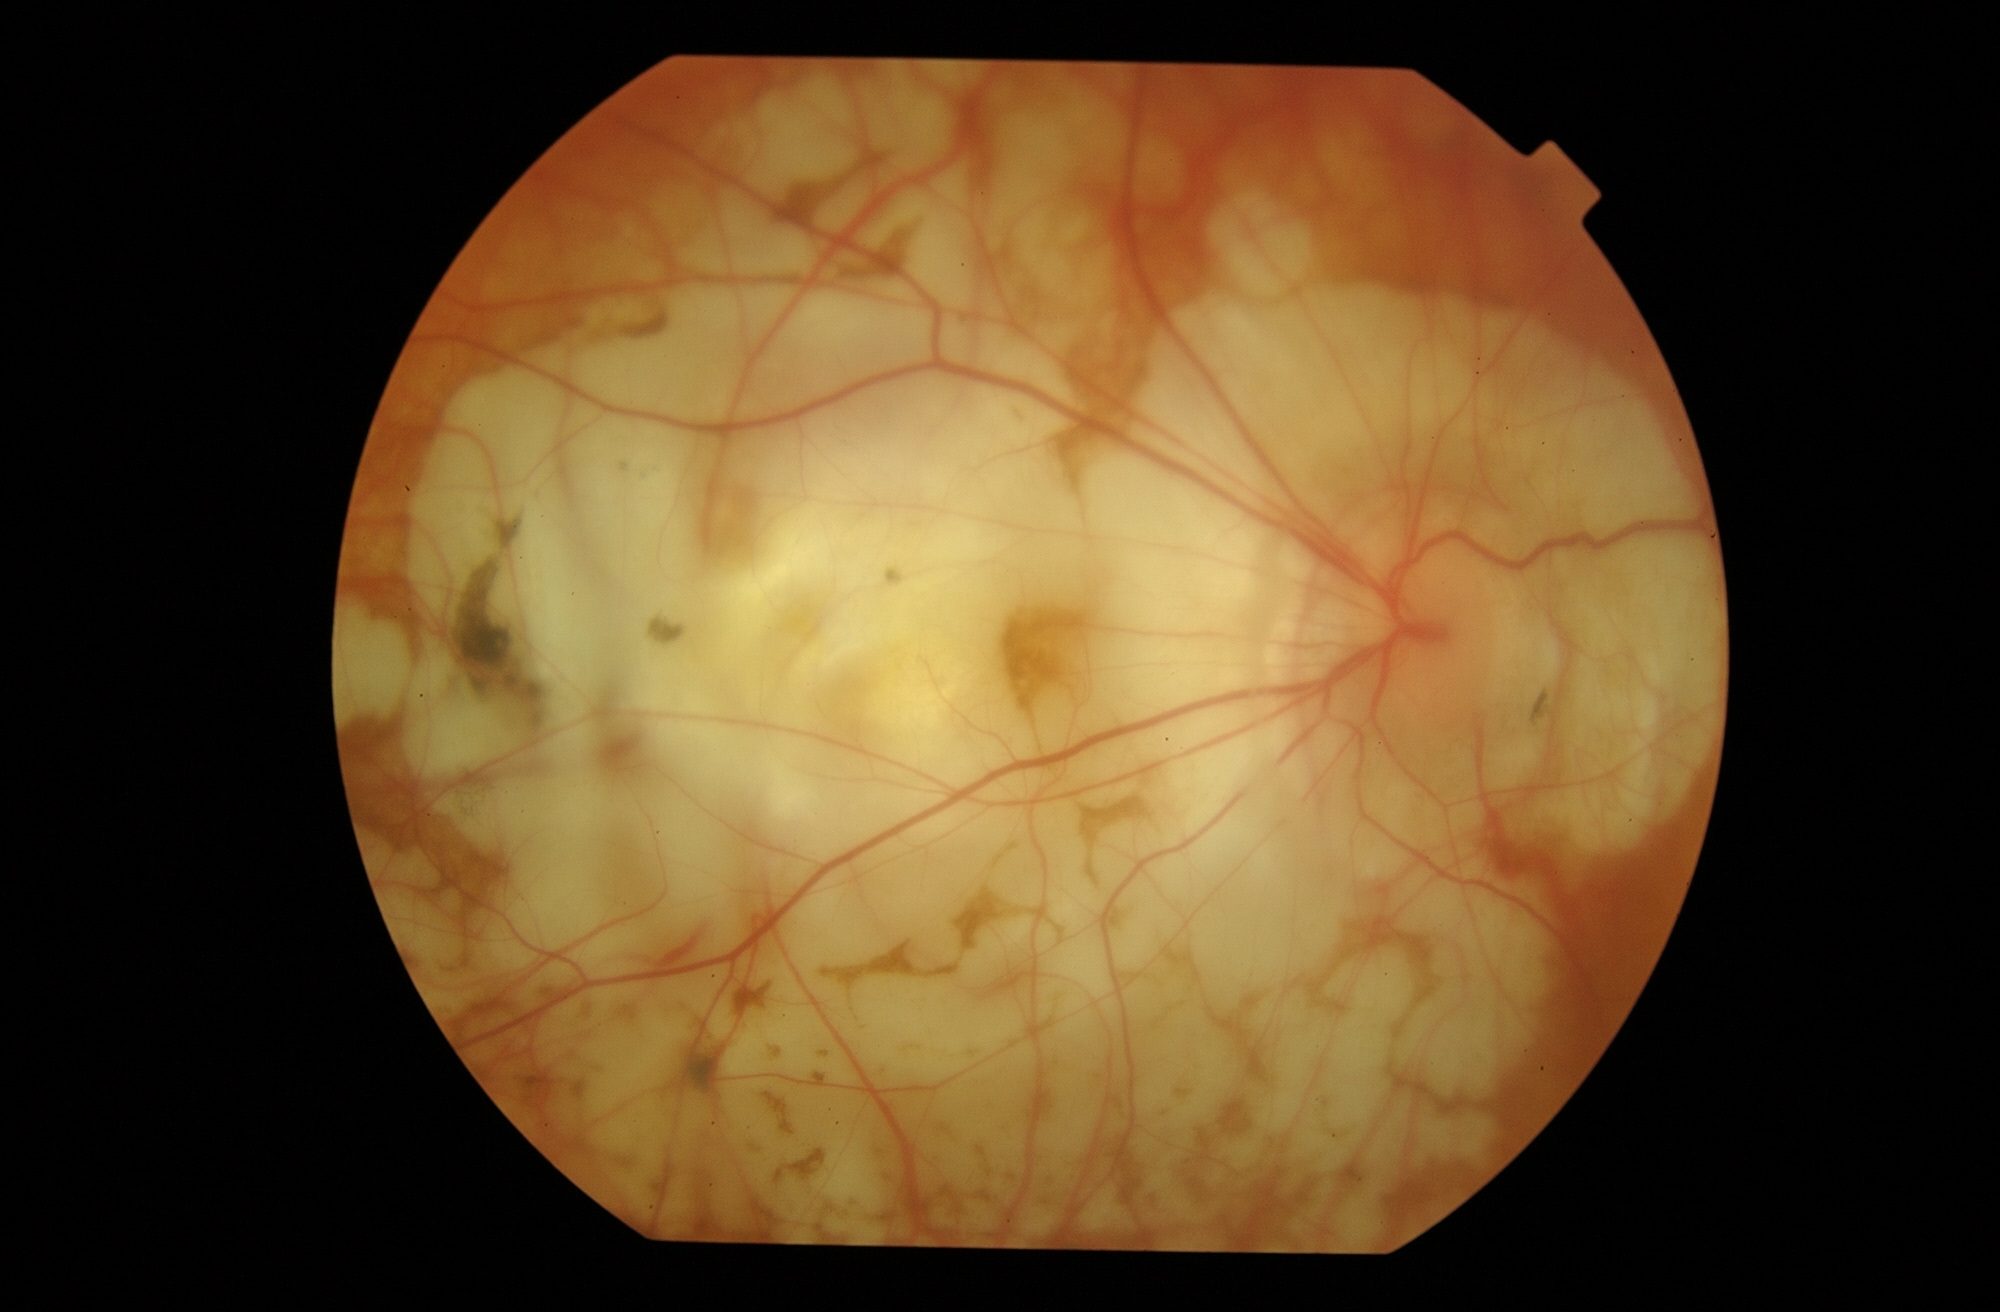

La DMAE es una enfermedad degenerativa caracterizada por una lesión en la parte central de la retina: la mácula.